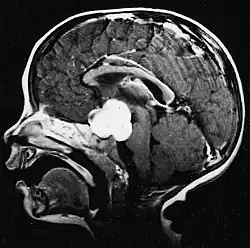

Aan -MRI toont een intracraniële tumor als een massieve laesie die na gebruik van het contrastmiddel meer luminescent kan worden. Er is echter altijd een signaalafwijking in -Magnetic resonance imaging, die de aanwezigheid van neoplasie of vasogeen oedeem aangeeft. Gewoonlijk is verhoogde luminescentie (contrastversterking) indicatief voor een tumor met een hogere graad van maligniteit. Kenmerkend voor glioblastoom is een contrastring, waarbij het lichtgevende deel overeenkomt met het vitale deel van de kwaadaardige tumor en het donkerdere -hypointens gebied dat overeenkomt met weefselnecrose.

Glioblastoom

De meest voorkomende en kwaadaardige gliaceltumoren zijn glioblastomen. Ze bestaan voornamelijk bij volwassenen uit een heterogene massa van slecht gedifferentieerde astrocytoomcellen. Ze komen meestal voor in de hersenhelften, meer zelden in de hersenstam of het ruggenmerg. Behalve in zeer zeldzame gevallen, zoals alle hersentumoren, reiken ze niet verder dan de structuren van het centrale zenuwstelsel.

Glioblastoom kan ontstaan uit een diffuus (II. graad) of een anaplastisch astrocytoom (III. graad) ontwikkelen. In het laatste geval wordt het secundair genoemd. Wanneer het echter optreedt zonder antecedenten of bewijs van eerdere maligniteit, wordt het primair genoemd. Glioblastomen worden behandeld met chirurgie, bestraling en chemotherapie. Ze zijn moeilijk te genezen en er zijn maar weinig gevallen die langer dan drie jaar overleven.